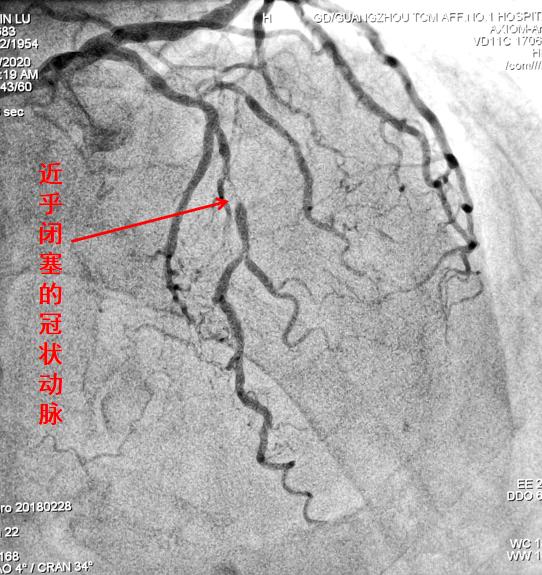

由于启动了“绿色通道”流程,一路绿灯,多方联动,黄伯马上被送到介入室,医生迅速将细小导管经其手腕处的桡动脉(也就是我们摸脉的地方)穿刺入路,在电视透视监视下插入到冠状动脉,造影发现有一条重要的分支血管闭塞了!诊断血管问题,插管造影才是“金标准”,这下诊断完全得到了证实!

冠脉造影可明确看到哪条血管有问题

关键还得治疗!医生迅速插入血栓抽吸导管到这条被血栓阻塞的血管分支,抽出血栓,让那些“半死不活”的心肌有了血供,患者的监测指标马上就有了改善。但造影复查发现血管局部仍然存在明显的斑块和狭窄,医生又当机立断为黄伯植入了金属支架,再次造影显示血管已经完全开通,这又为防止短期内再次缺血提供了保障,治疗取得了圆满成功。